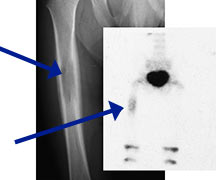

- May arise from any bone and any site within a bone (epiphyseal, metaphyseal, diaphyseal)

- Radiographically variable appearance: may appear benign (geographic) or malignant (permeative or moth eaten)

- Flat Bones (most common—70%)

- Femur